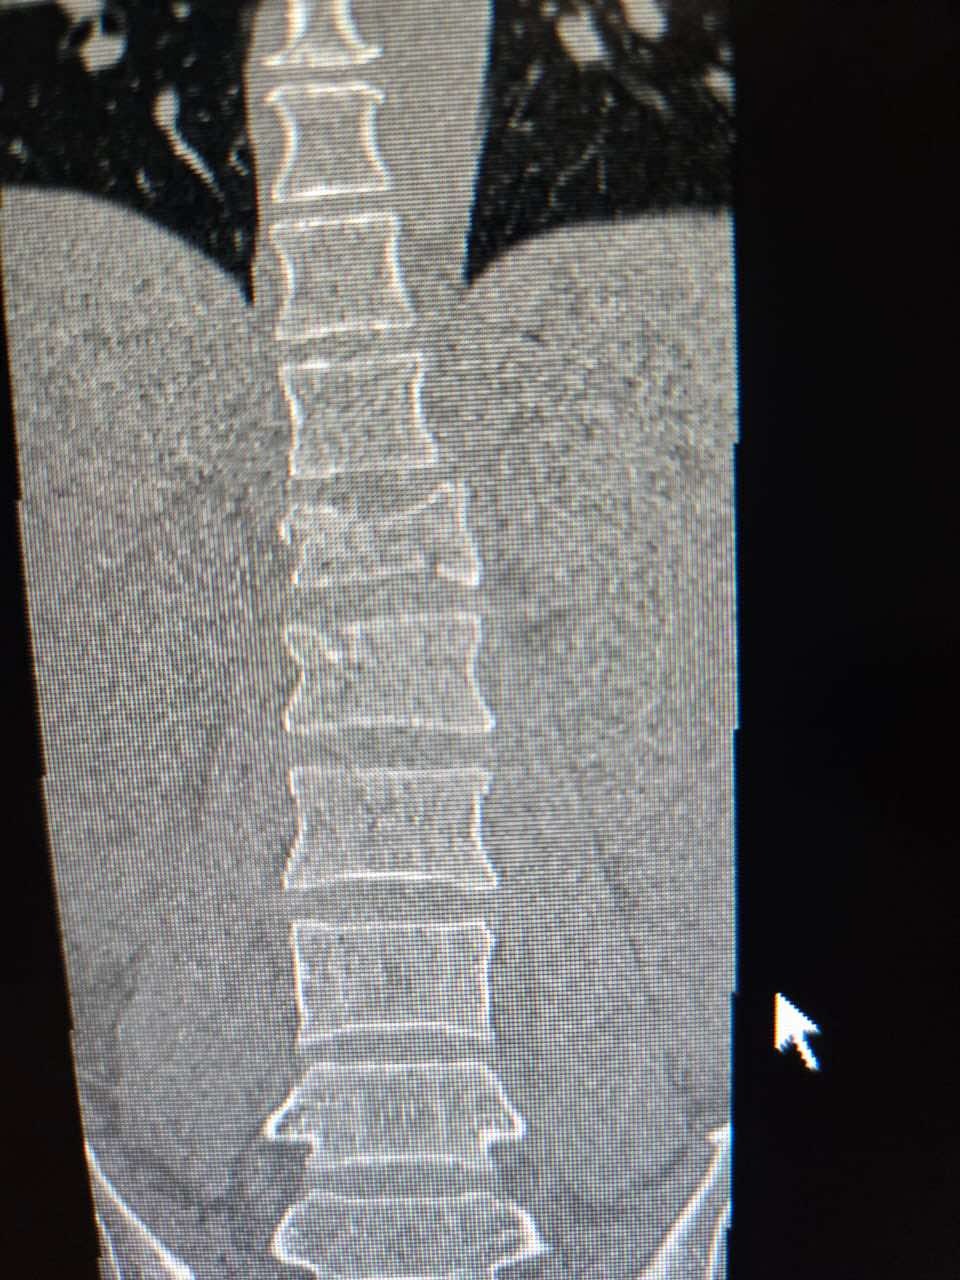

A few days ago, while surfing near Puerto Escondido, Mexico, our dear friend Vincent “Vinnie” Cook had a terrible accident. He free-fell from a large wave and landed hard on his tailbone. The impact caused a compression fracture of his T12 vertebra, a serious spinal injury that requires surgery to stabilize his spine and prevent long-term damage.

We’re beyond grateful that Vinnie is not paralyzed — but his recovery journey will be long and costly. Doctors have advised that he will need surgery as soon as possible, followed by three to six months of recovery, during which he won’t be able to work.